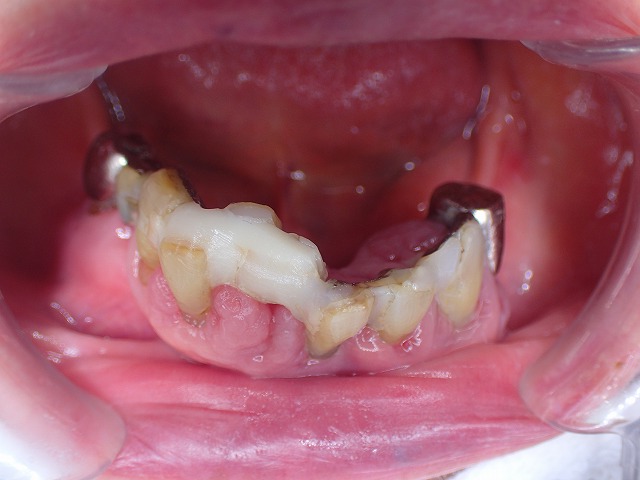

歯周病固定 実例2 長期にわたって観察管理・予防処置

10年間維持の状態

この段階で10年経過 2018年時点の状況

固定することにより歯の寿命を延命してきました。

定期的なお手入れが大切です。

歯の周囲の歯周組織は破壊され

相対的に歯が長くなっています。